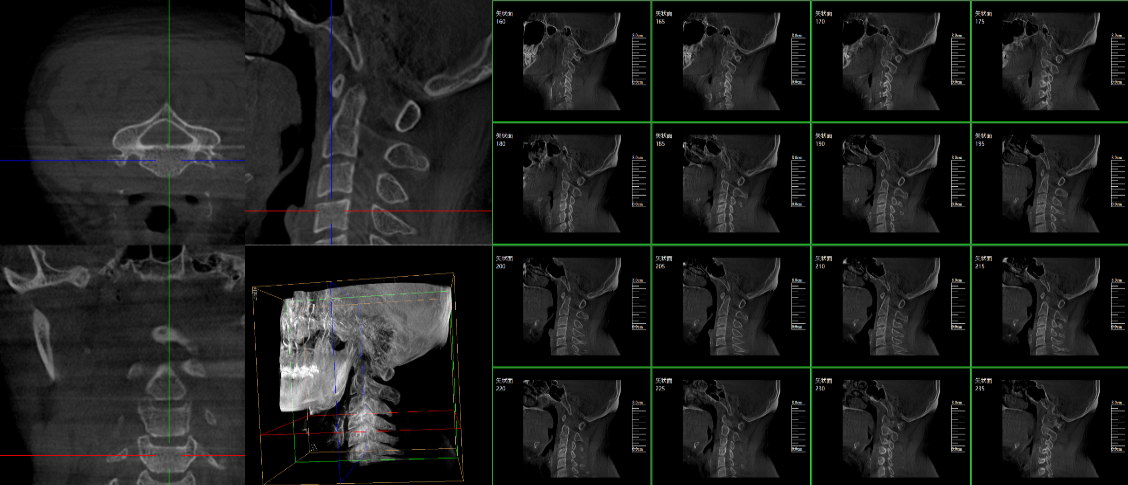

三維C臂,作為“術(shù)中CT”,能在術(shù)中快速地生成橫斷面、矢狀面、冠狀面和可旋轉(zhuǎn)的立體圖像,給術(shù)者提供360°無(wú)死角的觀察角度,全方位準(zhǔn)確判斷骨組織和植入物的情況,為手術(shù)的實(shí)施提供保障,極大提高手術(shù)成功率,減少并發(fā)癥概率。主要適用于骨科、脊柱外科、矯形外科、創(chuàng)傷骨科及手術(shù)室等。

普愛(ài)醫(yī)療三維C形臂具備術(shù)中實(shí)時(shí)三維成像,術(shù)中三維成像和橫斷面圖像提供多角度的手術(shù)診斷信息,輔助醫(yī)生進(jìn)行術(shù)中評(píng)估判斷,諸如骨折復(fù)位情況和內(nèi)植入螺釘?shù)某叽绾臀恢茫o助手術(shù)更好地完成;三維成像視野大,提供更大的術(shù)中三維成像視野,采集更多圖像信息,可一次拍全全段頸椎、全段腰椎、七節(jié)胸椎、雙側(cè)骶骼關(guān)節(jié)、股骨頭及單側(cè)盆骨等。如果您想了解更多普愛(ài)三維C形臂優(yōu)點(diǎn)及技術(shù)參數(shù),歡迎咨詢我們。